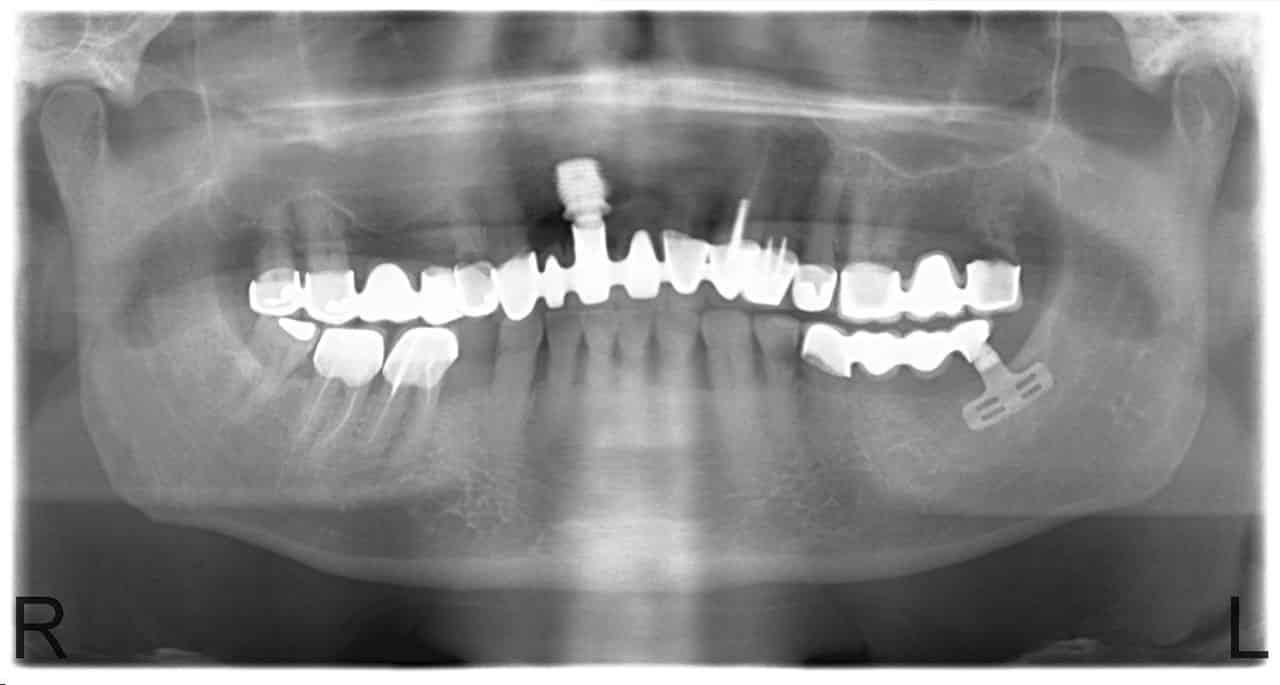

Professzionálisan kivitelezett implantátum Budapesten

A cukorbetegség, rendszeres dohányzás, csontritkulás mind olyan problémaforrások, amelyek sok esetben, több téren keseríthetik meg az életünket. Bár némelyikre van hatékony megoldás, míg másokra kevésbé, de amivel gyakran együtt járnak ezek a bajok, az a fogsor részleges vagy teljes elvesztése. Ha bekövetkezik a legrosszabb, akkor sem kell megijedni, hiszen az implantátum Budapest kitűnő alternatívát nyújt.

A kihullott rágóeszközök helyére kerül vissza az új fog. A stabil rögzítés garantált, így nem fog újból kihullani. Az implantátum Budapest 60 éves technikai fejlesztés keretében kidolgozott metódus mentén kerül beépítésre, kimagasló sikeraránnyal. Mivel nincs felesleges csontbeültetés, így a gyógyulási idő is lerövidül, valamint a fájdalom minimális.

Az IHDE implantációs eljárás 72 órán belül elkészülő és azonnal terhelhető fogpótlást ígér. Már eddig több mint 100 000 páciens élt az implantátum Budapest elkészítésének lehetőségével és ez a szám folyamatosan nő. Ha szeretnénk mi is ezen személyek közé tartozni, akkor a dentalcenterkelemen.hu oldalon mindent megtalálunk, amire a jelentkezéshez szükségünk lesz.